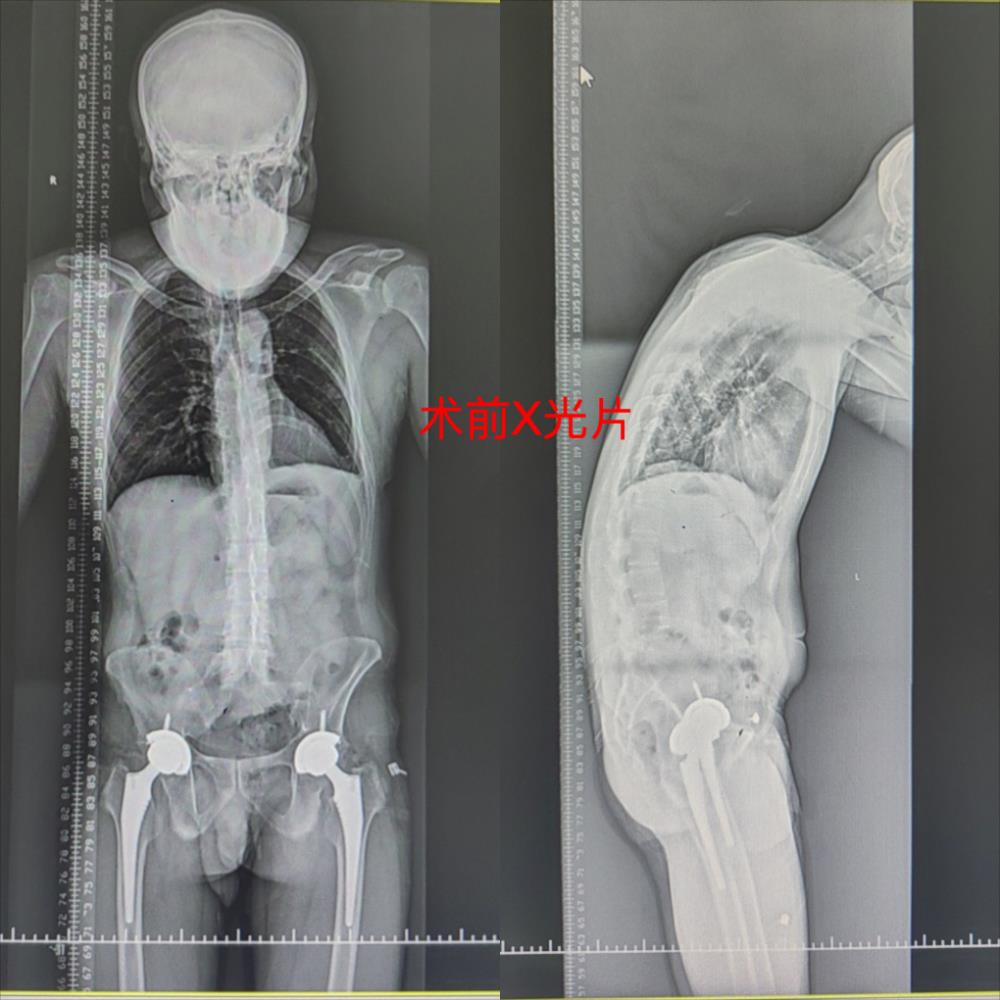

经人介绍,慕名找到了玉林市中西医结合骨科医院脊柱一科副主任谢新景医生。经过谢主任查体并结合相关检查,诊断为“强直性脊柱炎并后凸畸形”,且患者的脊柱存在严重的冠状位失衡和矢状位失衡,如不及时手术矫形,胸廓畸形症状会越来越严重,躯干部分会像大对虾一样弓背弯曲。经过与谭先生和家属充分沟通后,建议住院手术治疗。

经过3天的认真准备,邹焕汶主任手术团队为其制定了最佳的治疗方案。11月3日在邹焕汶主任、谢新景副主任的主刀下历经2个小时,终于顺利完成了强直性脊柱炎并后凸畸形切开截骨矫形、减压、植骨融合内固定术,术后谭先生安全返回病房。